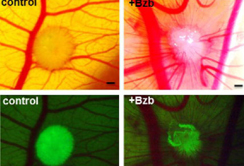

Die Wissenschaftler aus der Abteilung für Hämatologie und Onkologie der Medizinischen Universität Innsbruck (Leitung Prof. Günther Gastl) haben menschliche Myelomzellen mit dem grün leuchtenden Quallenproteil GFP ausgestattet, um sie unter dem Fluoreszenzmikroskop leicht erkennen und beobachten zu können. Diese markierten Zellen haben sie mit menschlichen Knochenmarks-Bindegewebszellen und mit Kollagen in Form kleiner dreidimensionaler Zell-Kugeln herangezüchtet. So simulieren sie die natürliche Knochenmarksumgebung des Tumors, die beim Myelom eine entscheidende Rolle spielt. Die Zell-Kugeln haben sie auf die äußere Haut eines bebrüteten Hühnereis übertragen, dem sie zuvor die Schale entfernt haben. Auf dieser sogenannten Chorioallantoismembran (CAM) wachsen die menschlichen Mini-Tumore in einer Petrischale heran.

Die Wissenschaftler geben verschiedene Test-Substanzen hinzu und beobachten, ob diese die Myelomzellen in ihrer dreidimensionalen, kugeligen Umgebung töten. Das ist nicht selbstverständlich, denn die umgebenden Bindegewebszellen schirmen den Tumor im Testsystem genauso wie im Körper des Patienten ab. Diesen "Schutzschild" müssen Krebsmedikamente überwinden, um wirken zu können. Zudem verfolgen die Forscher über mehrere Tage, ob der Krebs Blutgefäße anlockt, die ihn versorgen, oder ob die Test-Substanzen dies verhindern können. Schließlich erlaubt das System auch Rückschlüsse auf die Toxizität für den Gesamtorganismus.